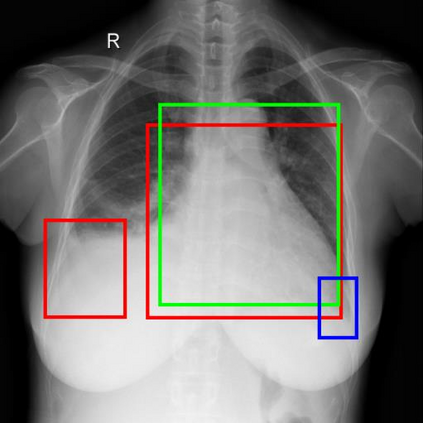

Chest X-ray (CXR) is the most typical diagnostic X-ray examination for screening various thoracic diseases. Automatically localizing lesions from CXR is promising for alleviating radiologists' reading burden. However, CXR datasets are often with massive image-level annotations and scarce lesion-level annotations, and more often, without annotations. Thus far, unifying different supervision granularities to develop thoracic disease detection algorithms has not been comprehensively addressed. In this paper, we present OXnet, the first deep omni-supervised thoracic disease detection network to our best knowledge that uses as much available supervision as possible for CXR diagnosis. We first introduce supervised learning via a one-stage detection model. Then, we inject a global classification head to the detection model and propose dual attention alignment to guide the global gradient to the local detection branch, which enables learning lesion detection from image-level annotations. We also impose intra-class compactness and inter-class separability with global prototype alignment to further enhance the global information learning. Moreover, we leverage a soft focal loss to distill the soft pseudo-labels of unlabeled data generated by a teacher model. Extensive experiments on a large-scale chest X-ray dataset show the proposed OXnet outperforms competitive methods with significant margins. Further, we investigate omni-supervision under various annotation granularities and corroborate OXnet is a promising choice to mitigate the plight of annotation shortage for medical image diagnosis.